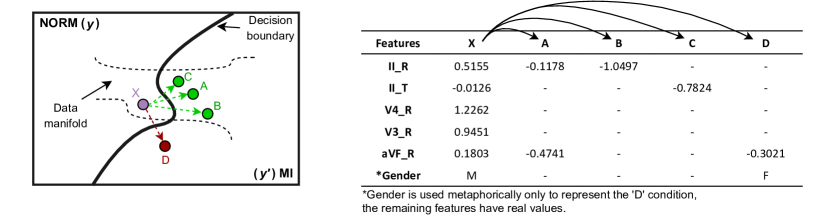

In order to find convenient explanations that are comprehensible and valuable to individuals with varying levels of expertise, it is reasonable to explore research that work on how humans provide and receive explanations [42]. Counterfactuals, a concept rooted in philosophy, epistemology and psychology [43, 44, 45, 46, 47, 48, 49], involve contemplating hypothetical scenarios such as “what if things were different?". In our human experience, there exist many instances and events where multiple outcomes are possible. This is particularly evident in the medical field, where each patient’s uniqueness plays a significant role. The realm of AI has embraced the notion of counterfactual generation, gaining notable attention in recent times. This approach tailors responses for individual patients by considering past cases, allowing us to explore questions like, “What if this patient had been diagnosed with MI instead of NORM? What alterations would be required for this specific case?" (Figure 2).

The motivation underlying the generation of counterfactual scenarios for ML outcomes, aimed at providing more coherent explanations to end-users, can be traced back to a study conducted by Watcher et al. [50]. In order to advance this concept and improve the generation of meaningful alternative scenarios, numerous algorithms have been developed in recent years [51, 52, 53, 54]. For a comprehensive compilation of counterfactual algorithms, refer to Guidotti’s review paper [55] and Verma et al.’s extensive literature review [56] on counterfactual explanations for ML that provides a survey of its application. In the domain of ECG literature, there also has been a growing interest in the exploration of counterfactual generation [36, 57, 40]. This particular avenue of study has attracted attention from various vantage points, as researchers seek to address this issue using a range of different approaches. To ensure better reproducibility, we opted for one of the most user-friendly algorithm among these methods: the DiCE (Diverse Counterfactual Explanations) [51].

5.2 Counterfactual Generation

The process of generating counterfactual instances enhances our understanding of feature impact and provides clear explanations for feature values, beyond traditional ranking algorithms. This approach uncovers additional insights into features that distinguish MI from NORM diagnoses, expanding our decision space exploration.

To accomplish this, we proceeded with the chosen feature sets of 5, 10, 15, and 20 during the Section 5.1. Table 2 provides a comprehensive overview of the outcomes, illustrating transformations from MI patients to NORM and vice versa. In the counterfactual analysis conducted across a population of beats, it becomes evident that the XGB model more easily diagnoses beats from NORM patients compared to those from MI patients. This observation is supported by the pred/true ratio, which is detailed in Table 2. Among the features under consideration, Feature 1-3 correspond to the top three features selected through the counterfactual optimization process. This selection indicates that these specific features exhibit better differentiation between NORM and MI cases, with distinct value distributions when we compare instances labeled as NORM to those categorized as MI. Consequently, we provided the most significant features by conducting additional feature selection across “possible worlds," for the collection of beats.

Analyzing the transition from NORM to MI, we observe notable changes in the aVF_R, II_R, and II_T features with shifts of 60, 56, and 45, respectively. Remarkably, even with a selection of just 5 features, the model accurately classified all beats. Interestingly, when expanding to 10 features, we encountered misdiagnoses in 2 beats. This anomaly may imply that the additional 5 features introduced are causing model confusion. With 10 features, the generated explanations highlight shifts in V3_ST, V1_S, and II_T with changes of 54, 36, and 35 respectively. Upon integrating 15 features, the model achieves perfect beat recognition and explanations unveil 37 changes in II_R and V3_ST, alongside 35 changes in II_T. Extending to 20 features, the model misclassified a single beat, coupled with 43 changes in V3_ST, 34 changes in V2_Q, and 31 changes in II_R.

For the inverse transition, MI to NORM, the features II_T, aVF_R, and II_R undergo substantial changes of 66, 43, and 42, respectively, contributing to the misclassification of 5 beats. Within the realm of 10 features, explanations concentrate on II_T, aVF_R, and II_R with changes of 56, 50, and 37. Progressing to 15 features, the model still struggles with diagnosis, resulting in 5 misclassifications. Explanations for this scenario entail 60 changes in II_R, 39 changes in II_T, and 38 changes in aVF_R. When employing 20 features, the model misclassifies 4 beats, accompanied by 71 changes in II_R, 59 changes in V3_R, and 36 changes in V4_PT.

In terms of overall counterfactual sparsity, our clinical approach demonstrated lower sparsity (0.19) compared to the XGB feature, which had a sparsity of 0.33. For a clearer understanding of sparsity on individuals, please refer to Figure 6. Patient-wise differences can be observed by comparing clinical and XGB boxplots. The general sparsity in XGB is evident in the figure, although some cases displayed even lower sparsity than their clinical-weighted counterparts.